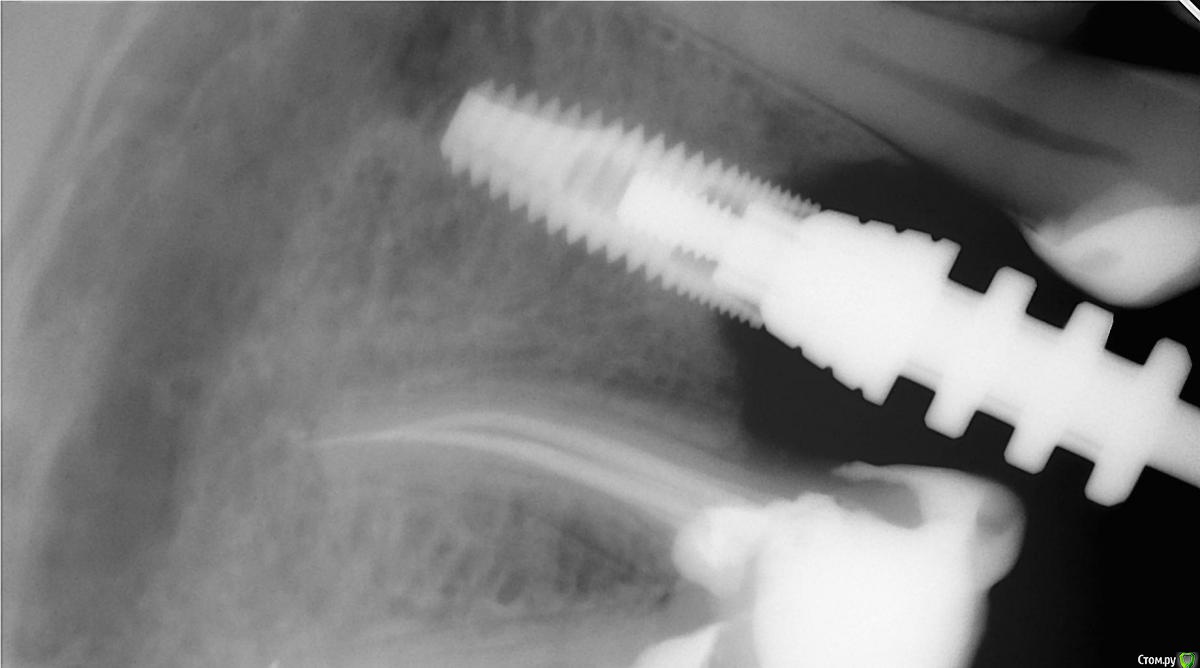

Kazaev77 Опубликовано 15 ноября, 2016 Поделиться Опубликовано 15 ноября, 2016 Добрый день . Новую тему открывать не стал. Подскажите пожалуйста что за имплантат. Сделал доступ к фиксирующему болту там шлиц под плоскую отвертку. Ссылка на комментарий

red_butler Опубликовано 15 ноября, 2016 Поделиться Опубликовано 15 ноября, 2016 Добрый день . Новую тему открывать не стал. Подскажите пожалуйста что за имплантат. Сделал доступ к фиксирующему болту там шлиц под плоскую отвертку.покажите снимок в нормальном качестве, например прицельный 1 Ссылка на комментарий

IvanK Опубликовано 15 ноября, 2016 Поделиться Опубликовано 15 ноября, 2016 и , желательно, в правильной плоскости) Ссылка на комментарий

Kazaev77 Опубликовано 16 ноября, 2016 Поделиться Опубликовано 16 ноября, 2016 Добрый день . Новую тему открывать не стал. Подскажите пожалуйста что за имплантат. Сделал доступ к фиксирующему болту там шлиц под плоскую отвертку. Ссылка на комментарий

red_butler Опубликовано 16 ноября, 2016 Поделиться Опубликовано 16 ноября, 2016 Вы не поняли, на показанной панорамной реконструкции Кт видно только очертания винта и похоже соединение - внутренний шестигранник. Сделайте прицельный снимок Ссылка на комментарий